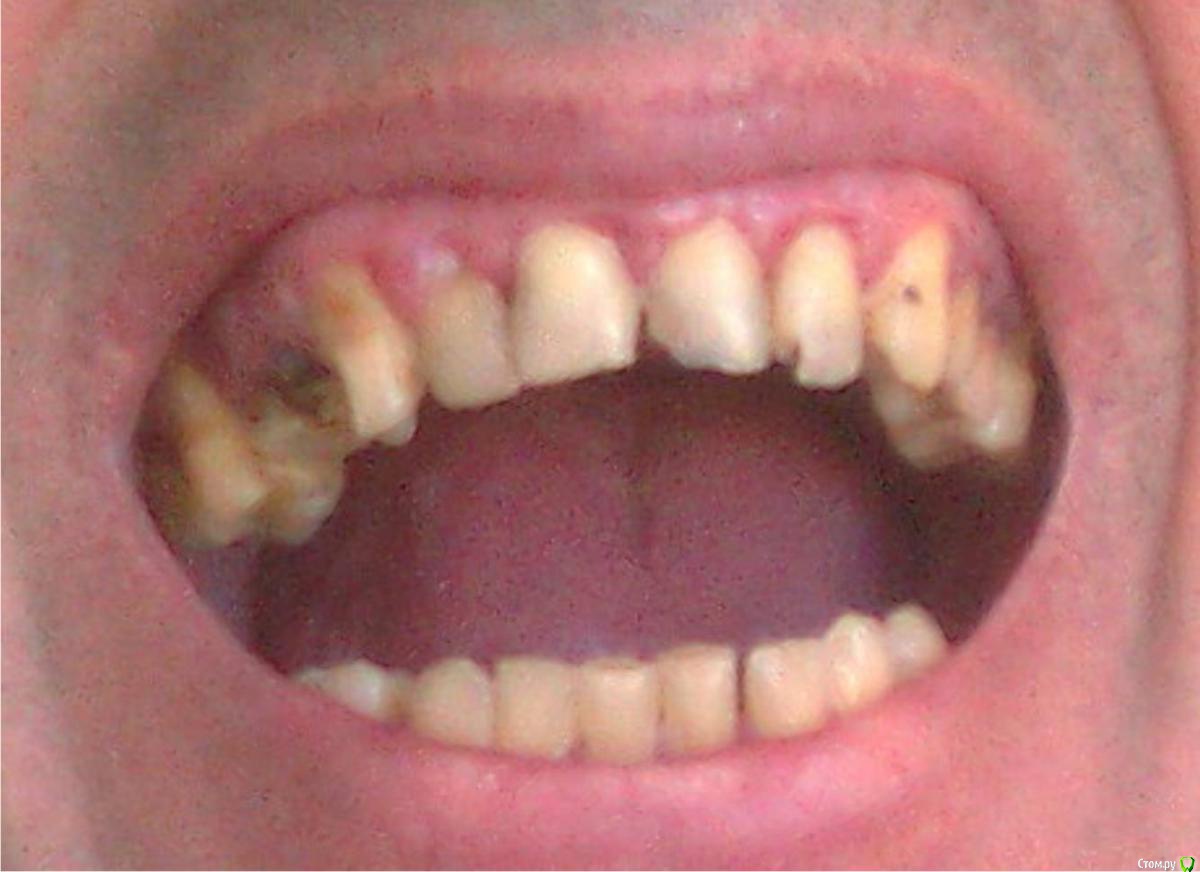

Гарриевич Опубликовано 20 мая, 2015 Поделиться Опубликовано 20 мая, 2015 (изменено) 1 - профессиональная гигиена полости рта, с участием пародонтолога2- удаление 17 16 26 27 и 25(под вопросом) зубов3- перелечивание 15 14 24 25 и 35(под вопросом) зубов4- протезирование коронками 15 14 24 25 35 зубов5- прямая или непрямая реставрация 13 12 11 21 22 23 зубов6- или имплантация а области 45 46 47 36 37 зубов на нижней челюсти и 17 16 26 27 зубов верхней челюсти (для планирования имплантации нужен снимок КТ) или бюгельный съемный протез на верхнюю и на нижнюю челюсть с перелними нижними зубами разговор тоже только после КТ Изменено 20 мая, 2015 пользователем Гарриевич 2 Ссылка на комментарий